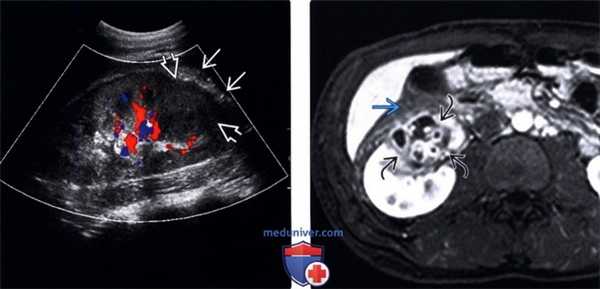

(Левый) На УЗ срезе с цветовой допплерографией отсутствует васкуляризация в нижнем полюсе гипоэхогенного образования (содержимое абсцесса).

Обратите внимание на гиперэхогенность окружающей клетчатки, что указывает на воспаление околопочечного вещества.

(Правый) На Т1-ВИ FS МР срезе с контрастированием у того же пациента визуализируется образование с неровными контурами в нижнем полюсе почки, содержащее по краям множество контрастирующих очагов.

С целью исключения кистозного новообразования почки была выполнена биопсия, при которой был подтвержден абсцесс.

Однако на инфекционную природу указывали также воспалительные изменения в переднем околопочечном пространстве.